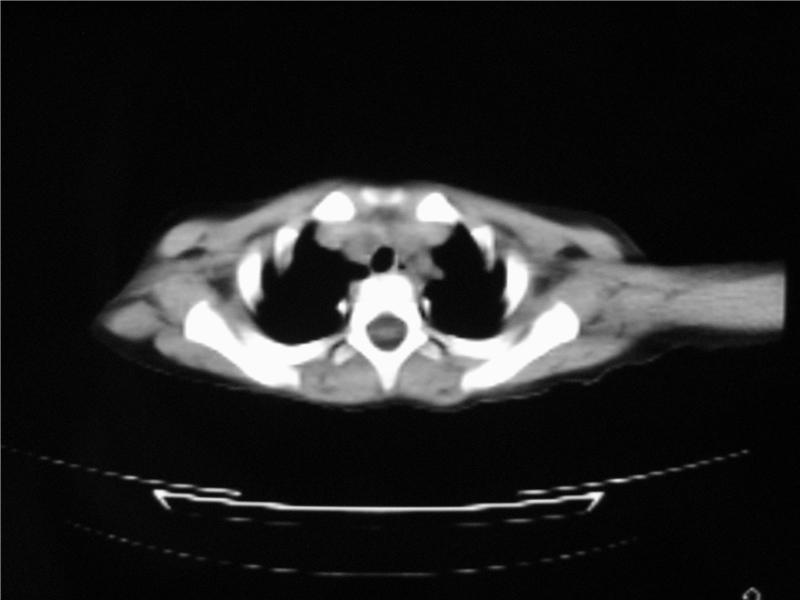

标题: PED3236:男2岁进食花生米后发烧10天。

右侧中间段支气管阴性异物可能,建议支气管镜

1)右肺炎症并右肺中叶肺不张,右肺上叶充气不良。2)右侧支气管异物不排除。

结合病史,考虑气管异物所致。

再有,我们16排ct有气管重建功能,肯异物效果可以。